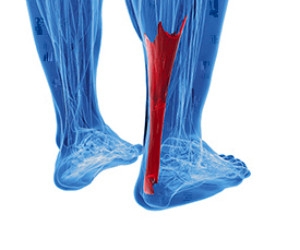

Types of Achilles Tendon Injuries

Tendons are bands of tissue that connect muscles and bones together. The Achilles tendon is located on the back of the ankle and connects the calf muscles to the heel. Tendonitis occurs when the tendon becomes inflamed. Tendinosis occurs when the tendon degenerates, usually due to overuse. Paratenonitis is a result of tissue around the tendon becoming inflamed and thickened, eventually attaching to the tendon. Insertional Achilles tendinopathy happens when the fibers attaching to the heel bone inflame and eventually degenerate. Another serious injury that can happen is an Achilles tendon rupture, which will make walking and standing extremely difficult and will likely require surgery. Because of the seriousness of Achilles tendon injuries, seeing a podiatrist for diagnosis and treatment is very important.

Tendons are bands of tissue that connect muscles and bones together. The Achilles tendon is located on the back of the ankle and connects the calf muscles to the heel. Tendonitis occurs when the tendon becomes inflamed. Tendinosis occurs when the tendon degenerates, usually due to overuse. Paratenonitis is a result of tissue around the tendon becoming inflamed and thickened, eventually attaching to the tendon. Insertional Achilles tendinopathy happens when the fibers attaching to the heel bone inflame and eventually degenerate. Another serious injury that can happen is an Achilles tendon rupture, which will make walking and standing extremely difficult and will likely require surgery. Because of the seriousness of Achilles tendon injuries, seeing a podiatrist for diagnosis and treatment is very important.

Achilles tendon injuries need immediate attention to avoid future complications. If you have any concerns, contact one of our podiatrists of PA Foot & Ankle Associates. Our doctors can provide the care you need to keep you pain-free and on your feet.

What Is the Achilles Tendon?

The Achilles tendon is a tendon that connects the lower leg muscles and calf to the heel of the foot. It is the strongest tendon in the human body and is essential for making movement possible. Because this tendon is such an integral part of the body, any injuries to it can create immense difficulties and should immediately be presented to a doctor.

What Are the Symptoms of an Achilles Tendon Injury?

There are various types of injuries that can affect the Achilles tendon. The two most common injuries are Achilles tendinitis and ruptures of the tendon.

Achilles Tendinitis Symptoms

- Inflammation

- Dull to severe pain

- Increased blood flow to the tendon

- Thickening of the tendon

Rupture Symptoms

- Extreme pain and swelling in the foot

- Total immobility

Treatment and Prevention

Achilles tendon injuries are diagnosed by a thorough physical evaluation, which can include an MRI. Treatment involves rest, physical therapy, and in some cases, surgery. However, various preventative measures can be taken to avoid these injuries, such as:

- Thorough stretching of the tendon before and after exercise

- Strengthening exercises like calf raises, squats, leg curls, leg extensions, leg raises, lunges, and leg presses

Achilles Tendon Injuries

The Achilles tendon is the largest tendon in the body; it is a tough band of fibrous tissue that stretches from the bones of the heel to the calf muscles. This tendon is what allows us to stand on our toes while running, walking, or jumping, it is common for this tendon to become injured. In severe cases, the Achilles tendon may become partially torn or completely ruptured. However, this tendon is susceptible to injury because of its limited blood supply and the high level of tension it endures.

The people who are more likely to suffer from Achilles tendon injuries are athletes who partake in activities that require them to speed up, slow down, or pivot. Consequently, athletes who engage in running, gymnastics, dance, football, baseball, basketball, or tennis are more likely to suffer from Achilles tendon injuries. Additionally, there are other factors that may make you more prone to this injury. People who wear high heels, have flat feet, tight leg muscles or tendons, or take medicines called glucocorticoids are more likely to have Achilles tendon injuries.

A common symptom of an Achilles tendon injury is pain above the heel that is felt when you stand on your toes. However, if the tendon is ruptured, the pain will be severe, and the area may become swollen and stiff. Other symptoms may be reduced strength in the lower ankle or leg area, and reduced range of motion in the ankle. When the Achilles tendon tears, there is usually a popping sound that occurs along with it. People who have acute tears or ruptures may find walking and standing to be difficult.

If you suspect you have injured your Achilles tendon, you should see your podiatrist to have a physical examination. Your podiatrist will likely conduct a series of tests to diagnose your injury including a “calf-squeeze” test. Calf squeeze tests are performed by first squeezing the calf muscle on the healthy leg. This will pull on the tendon and consequently cause the foot to move. Afterward, the same test will be performed on the injured leg. If the tendon is torn, the foot won’t move because the calf muscle won’t be connected to the foot.